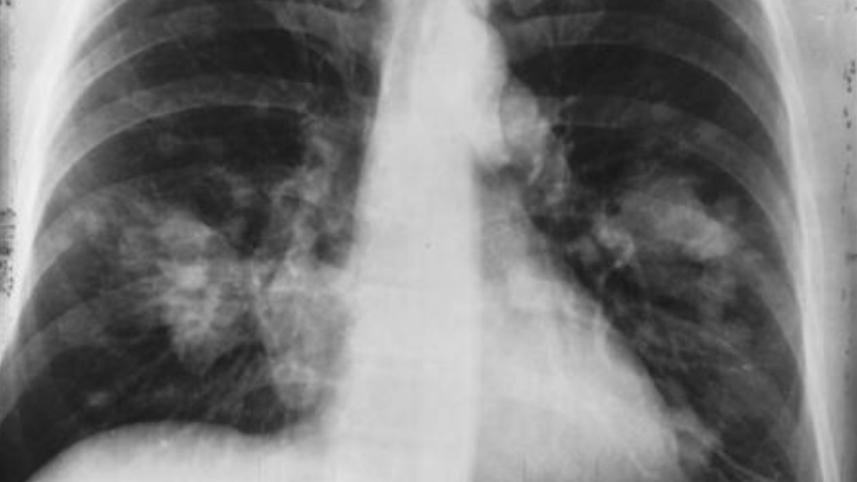

US doctors announced Thursday they had successfully performed a double lung transplant on a patient with terminal lung cancer, giving new hope to others who also have advanced stages of the deadly disease.

Albert Khoury, a 54-year-old non-smoker, underwent a seven-hour surgery to receive his new lungs at Northwestern Medicine in Chicago on September 25, 2021.

By July 2020, his cancer progressed to stage 2, and, despite several rounds of chemotherapy, kept growing to stage 3 and stage 4.

It was determined that he was in fact a candidate for transplant since the cancer, despite being stage 4, had not spread to other organs, and he received his new lungs after a two-week wait.

The team had to remove "trillions" of cancer cells all over his lungs within a six hour time frame, all the while taking care not to spill material into his chest cavity or blood stream.